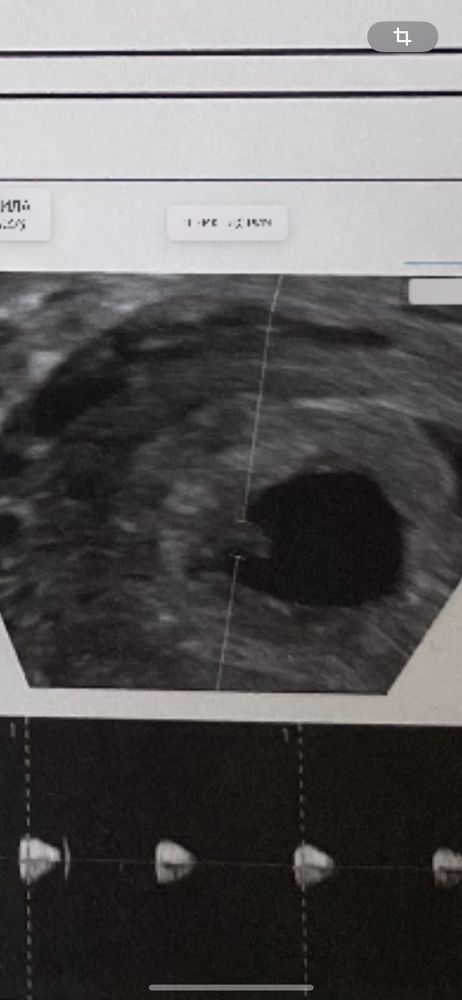

Беременность 6 недель

сегодня ходили на 2 узи ( первое делала на 4-5 неделе) и наконец нашли эмбрион и сердцебиение 🥰 сказали все хорошо , но так же нашли кисту на левом яичнике (3мм) , врач сказала не страшно , сама рассосется , но прописала утрожестан свечи . У кого была киста и как протекала беременность ?🤰